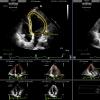

August 22, 2016 — The Detroit Medical Center (DMC) Heart Hospital recently completed a Complex Percutaneous…